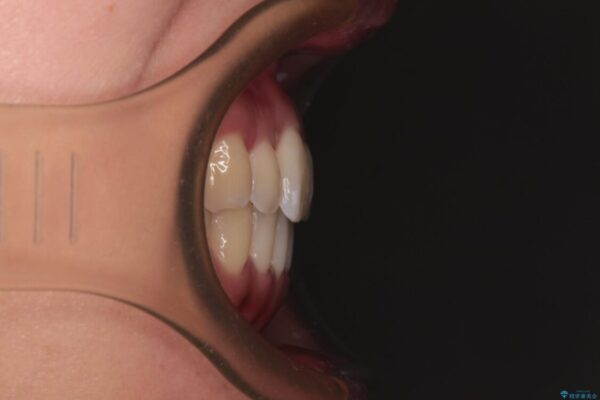

前歯のデコボコで前方に出ていることを気にして来院された患者様です。

上顎前歯が捻れて前方に飛び出しており、下顎前歯もそれに沿うようにデコボコとなっていました。

IPR(歯と歯の間を削る処置)によりスペースを獲得して上下顎前歯のデコボコを改善し、飛び出している前歯が引っ込むように設定し、インビザラインにて矯正治療を行うこととしました。

• 【モニター】前歯のデコボコをインビザラインで改善 治療前画像